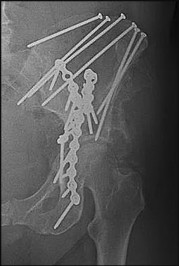

Explanation:

Day Type II crescent fractures involve a major fracture line exiting the iliac wing, but a substantial portion of the posterior ilium remains attached to the sacrum via the posterior SI ligaments. Biomechanical studies have demonstrated that for Day Type II fractures (where the fracture extends into the SI joint), combining an iliosacral screw to stabilize the SI joint component with an orthopedic plate for the iliac wing fracture provides the most stable construct, superior to either method alone.